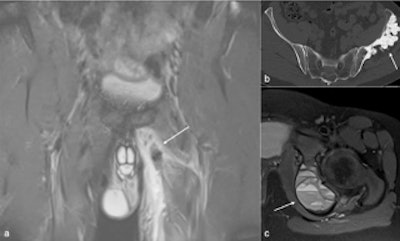

Figure shows left adductor tear (arrow in a), melorheostosis of left ilium (arrow in b), aneurysmal bone cyst in the left ischium (arrow in c).